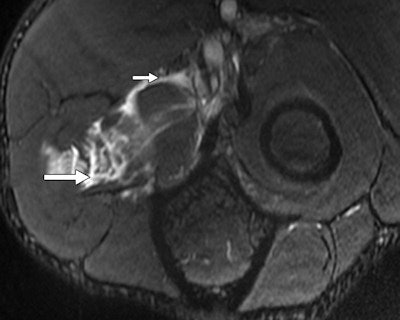

A 30-year-old male judo athlete with valgus stress and hyperextension injury of elbow. Top: Coronal proton density-weighted fat-saturated MRI shows full-thickness tear (white arrow) of proximal humeral attachment of anterior bundle of ulnar collateral ligament (UCL) and edema (black arrow) within surrounding muscle fibers. Below: Axial proton density-weighted fat-saturated MRI shows UCL posterior bundle disruption (long white arrow), with fluid surrounding ulnar nerve (short white arrow). However, ulnar nerve was contiguous on sequential images, with no transection. High-grade tear of flexor carpi ulnaris (black arrow) also was seen. Bottom: Axial proton density-weighted fat-saturated MRI shows high-grade tear of flexor digitorum superficialis (long arrow) and fluid surrounding median nerve (short arrow). All images reprinted with permission from the American Journal of Roentgenology.